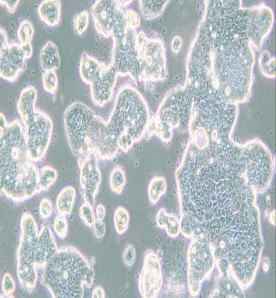

LS513人結(jié)直腸癌細(xì)胞

細(xì)胞形態(tài) : 上皮細(xì)胞樣

生長特性 : 貼壁細(xì)胞

細(xì)胞背景描述  :

LS513isa colo rectalcarcinom acelllineisolatedin 1985fro m aprim arytum orbiopsy from a 63 yearold C aucasianmale patien tdiagnosed with aD ukes'C mucin secreting cecaltum orlocated atthe Bauhin valve.

倍增時(shí)間 :20 hours(PubM ed = 25984343)

供體年齡 :男;63歲

組織來源 :盲腸

細(xì)胞類型 :腫瘤細(xì)胞

腫瘤類型 :結(jié)直腸癌細(xì)胞